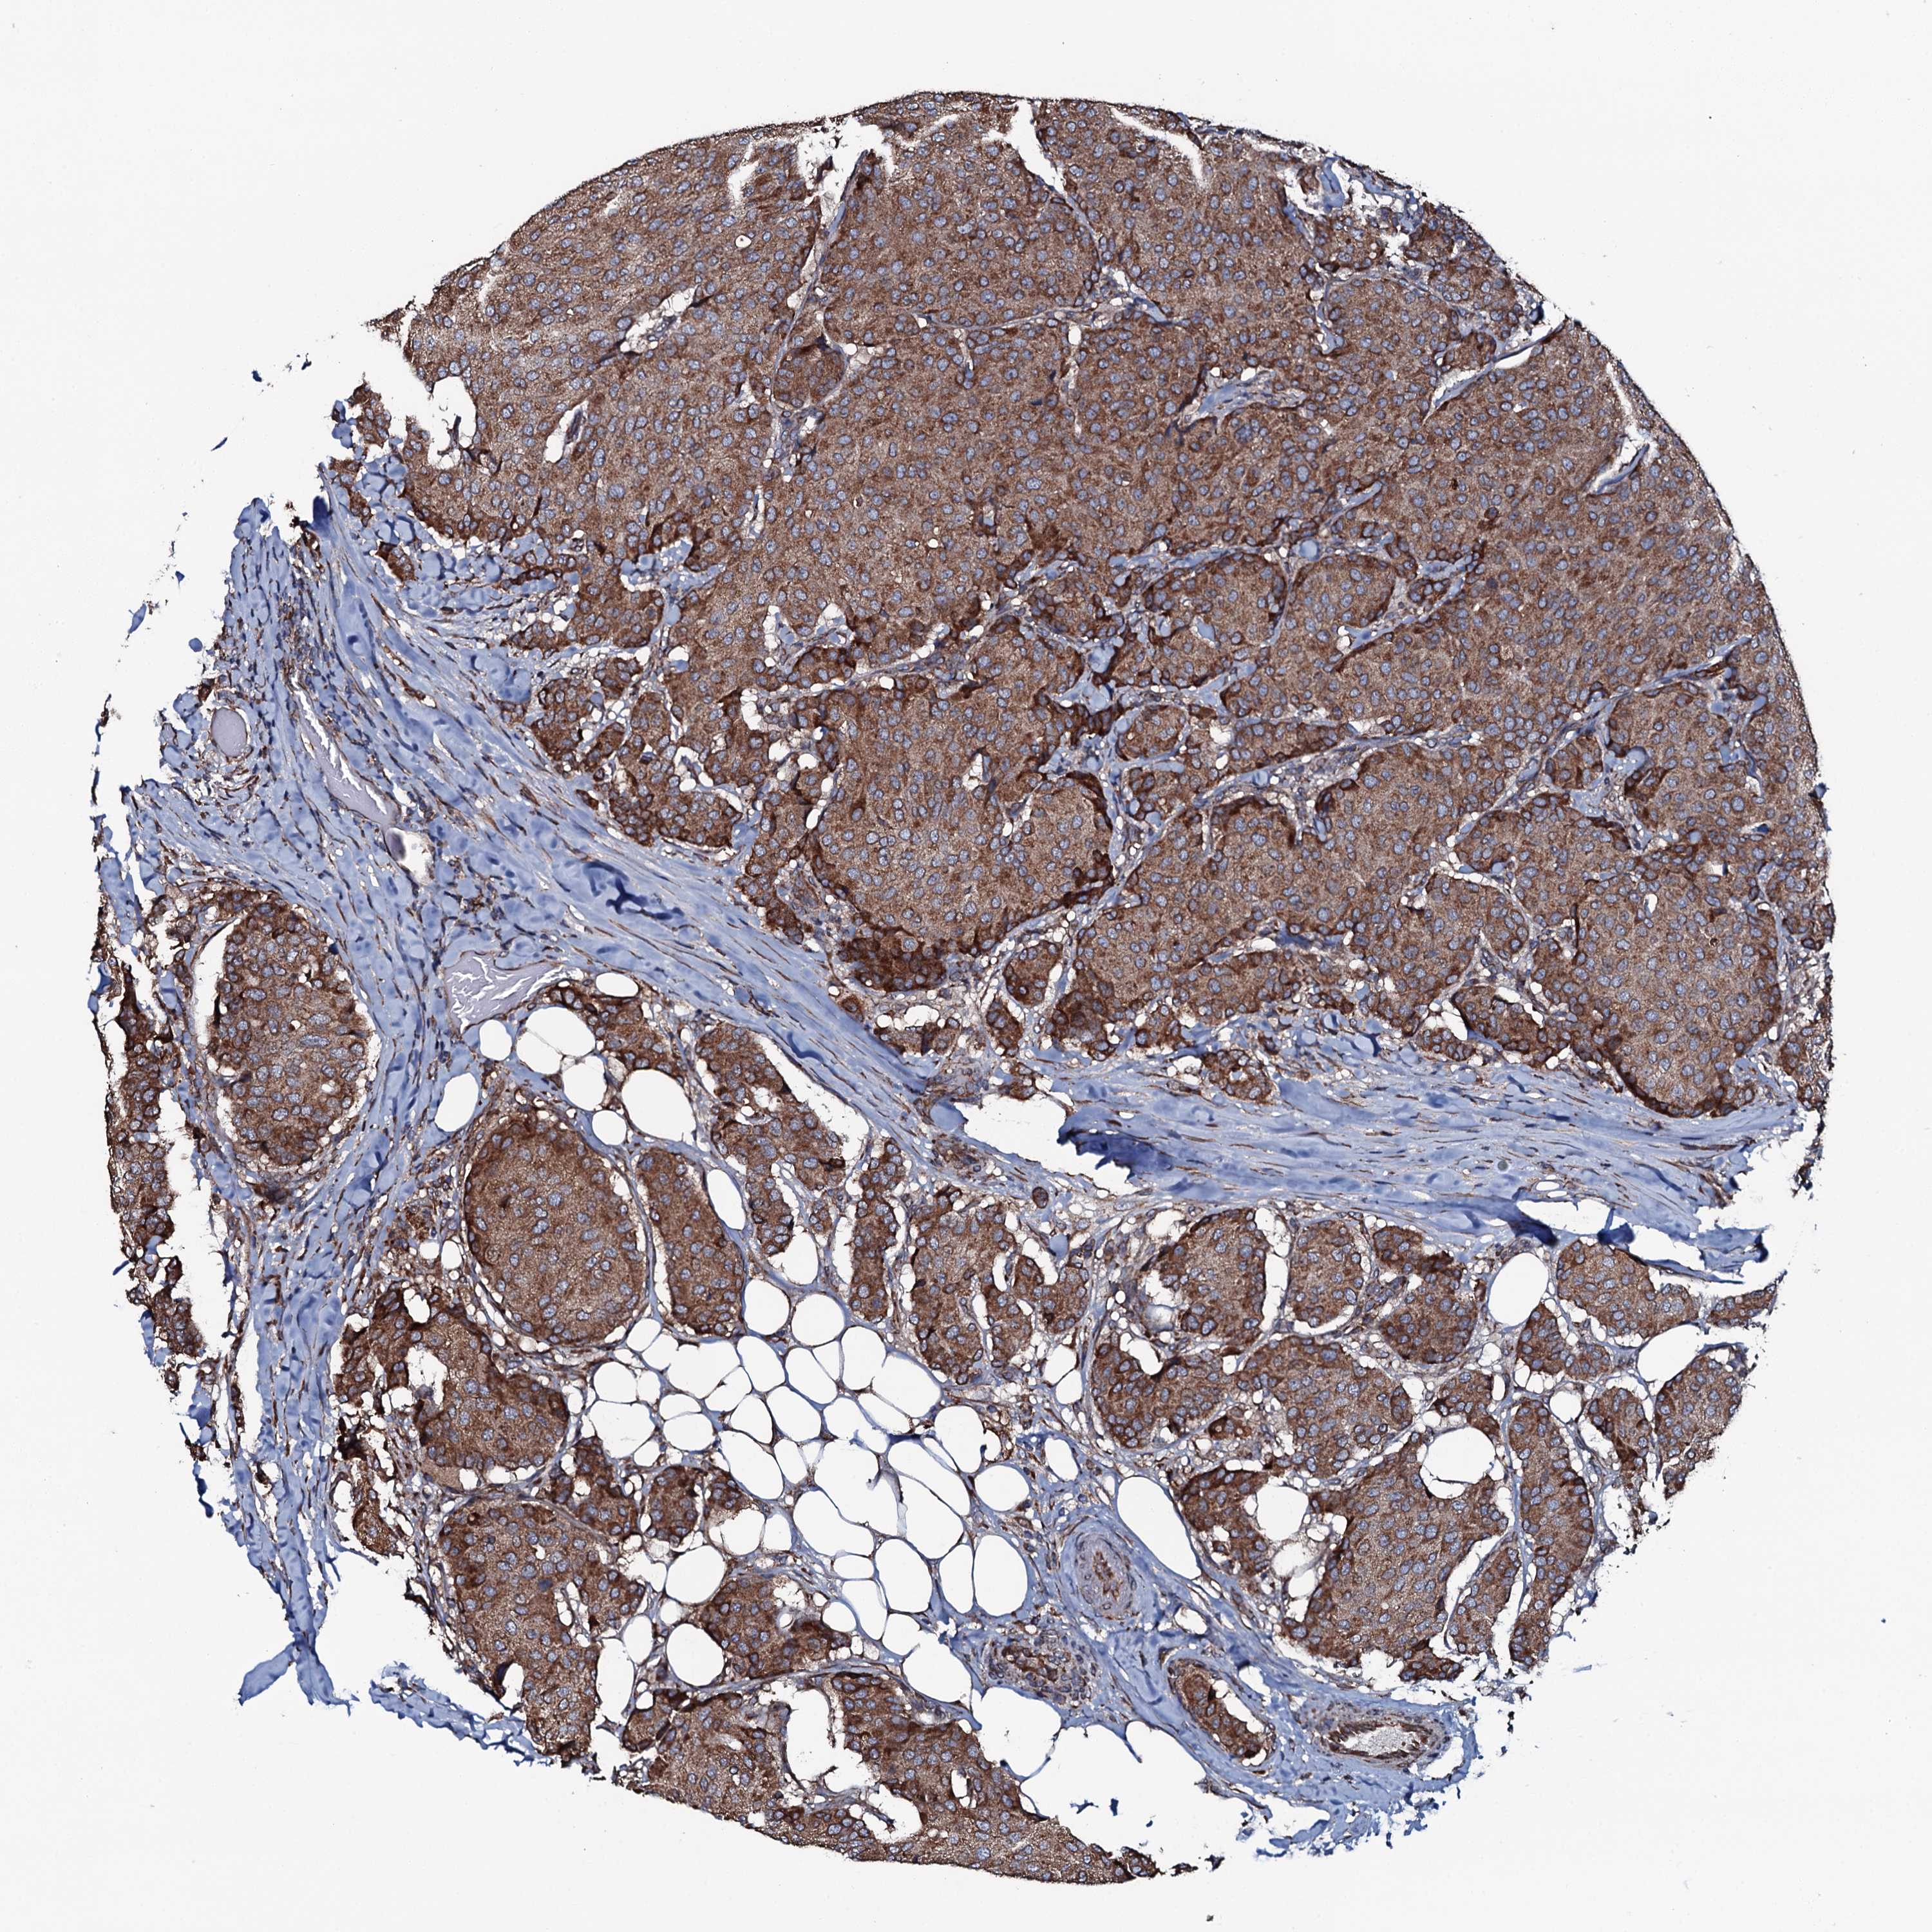

BRCA TCGA BRCA VALIDATION PROTEIN EXPRESSION